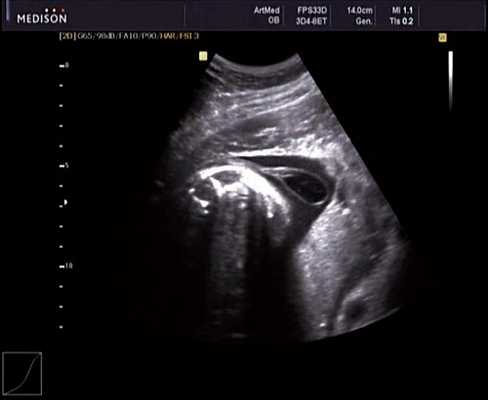

При эхокардиографии изучались четырехкамерный срез сердца плода (рис. 1) и срез через три сосуда (рис. 2). УЗИ проводилось трансабдоминальным датчиком, лишь при необходимости (затрудненная визуализация) использовался внутриполостной датчик. Четырехкамерный срез сердца плода при ультразвуковом сканировании трансабдоминальным датчиком визуализировался в 85% случаев, срез через сосуды - в 73%, при использовании трансвагинального датчика эти цифры существенно возрастали до 100 и 91% соответственно. Оптимизация пренатальной диагностики ВПС может быть достигнута путем строгого соблюдения основных методических правил. При оценке четырехкамерного среза плода необходимо оценить нормальное расположение сердца плода, исключив его эктопию (рис. 3), положение оси сердца плода, что не представляет никаких трудностей, нормальные пропорции и размеры камер сердца, движение створок атриовентрикулярных клапанов должно быть свободным, септальная створка трикуспидального клапана должна располагаться ближе к верхушке сердца (рис. 4). При оценке среза через три сосуда необходимо оценить взаиморасположение сосудов и их диаметр.

Рис. 1. Беременность 12 недель. Четырехкамерный срез сердца плода. Отчетливо видны камеры сердца.